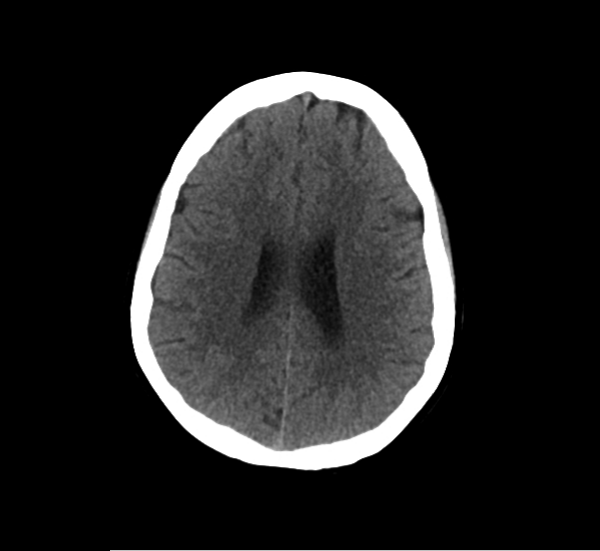

CT Brain Anatomy